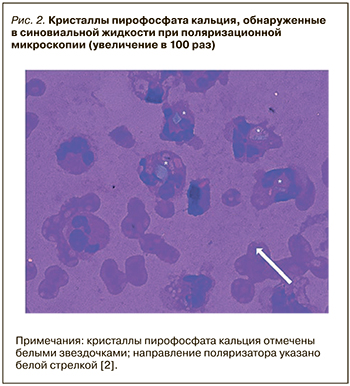

В результате повторного цитологического исследования суставной жидкости были обнаружены кристаллы пирофосфата кальция, кристаллы моноурата натрия не определялись (рис. 2).

В результате повторного цитологического исследования суставной жидкости были обнаружены кристаллы пирофосфата кальция, кристаллы моноурата натрия не определялись (рис. 2).

Трудность приведенного клинического случая при верификации диагноза заключалась как в схожести клинических проявлений ПАП и ранее установленной подагры (данных в пользу обострения которой получено не было), так и в симулировании ПАП клиники ревматоидного артрита (стойкие симметричные артриты обеих кистей, повышение сывороточного уровня СРБ), который в соответствии с диагностическими критериями АСR/EULAR 2015 г. подтвержден не был [5]. С учетом стойкой нормоурикемии, отсутствия данных в пользу ревматоидного артрита было предположено наличие у пациента еще одного заболевания, вызвавшего обострение. Согласно рекомендациям ACR/EULAR, решающее значение в диагностике микрокристаллических заболеваний имеет артроцентез с исследованием синовиальной жидкости для выявления кристаллов [1, 2, 6]. В результате обследования по данным цитологического исследования синовиальной жидкости были выявлены соли пирофосфата кальция, по данным рентгенографии коленных суставов – типичные признаки хондрокальциноза; это позволило установить диагноз «пирофосфатная артропатия. Подагра, хроническое течение. Подагрический артрит вне обострения».